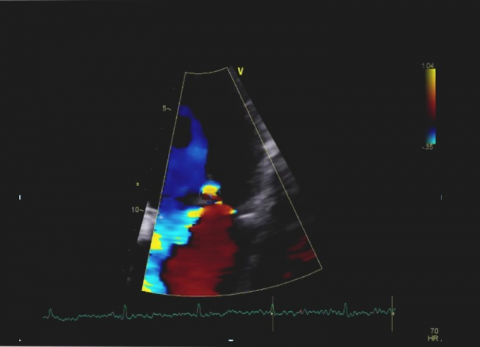

Wideo Echokardiografia. Przypadek 31

dr hab. n. med. prof. UJ Andrzej GackowskiPacjent z narastająca dusznością z podejrzeniem niedomykalności aortalnej.